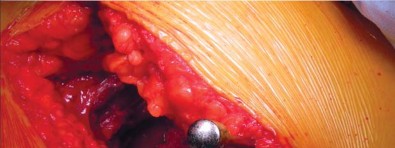

إدارة الأنسجة الرخوة وخلع رأس الفخذ

تُشق اللفافة العريضة والألياف الأمامية للعضلة الألوية الكبرى التي تتصل باللفافة العريضة قريبًا باستخدام الكي الكهربائي بما يتماشى مع شق الجلد. يتم إزاحة الجراب المدوري خلفيًا للمساعدة في رؤية العضلة الألوية الوسطى والعضلة المتسعة الجانبية. يتم رفع الجزء الأمامي من العضلة الألوية الوسطى عن المدور الكبير باستخدام الكي الكهربائي، ثم يتم تشريحه بشكل غير حاد بما يتماشى مع أليافه بزاوية 45 درجة أمامية-قريبة عند تقاطع الثلثين الأوسط والأمامي للعضلة. يقتصر التشريح على أقل من 3-4 سم باتجاه الرأس من طرف المدور الكبير لتجنب إصابة العصب الألوي العلوي. في غلاف مستمر مع العضلة الألوية الوسطى، يتم رفع الجزء الأمامي من العضلة المتسعة الجانبية عن حافة العضلة المتسعة ويتم شقه بعيدًا بين ثلثيه الأوسط والأمامي. يتم وضع مبعد هومان غير حاد في شق العضلة الألوية الوسطى لسحب الألياف الخلفية وكشف طبقة من الدهون بين المستويات الألوية. تُشق الكبسولة خلف العضلة الألوية الصغرى وعلى طول الجانب العلوي من عنق الفخذ. يقوم المساعد بتباعد وثني وتدوير الطرف خارجيًا لخلع رأس الفخذ.

تحضير الفخذ والحق